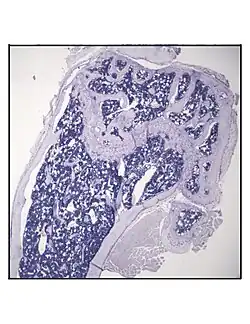

Secção histológica representativa da porção distal do fêmur de um camundongo C57BL/6 de 16 semanas de idade, após 6 semanas de restrição calórica, demonstrando um aumento na quantidade de adipócitos na medula óssea.